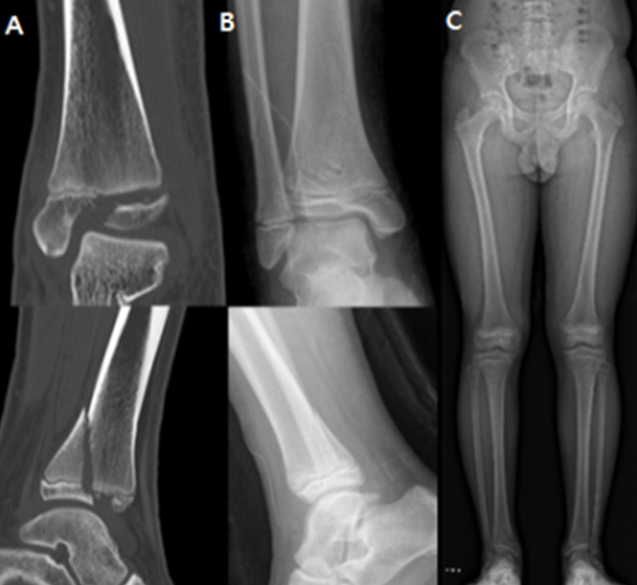

발목 성장판 골절은 뼈의 성장에 중요한 역할을 하는 성장판을 포함하는 발목 부위가 손상된 것을 말한다. 주로 10세 전후의 소아에게 흔하게 발생한다.

손상 부위의 뼛조각이 정상 위치에서 크게 어긋날 경우, 성장판이 손상돼 다리 변형이나 길이 차이가 생길 수 있어 수술적 치료가 필요하다.

연구팀은 발목 성장판 골절로 수술을 받은 15세 이하의 환아 67명을 대상으로, 금속 나사(40명)와 생체흡수성 나사(27명)를 이용한 수술 결과를 비교했다. 그 결과, 두 군 모두에서 성장판 손상 비율, 수술 시간, 수술 후 발목 기능이 우수했으며, 수술 후 감염, 상처 등 합병증 또한 없어 유의미한 차이 없이 동등한 치료 결과를 보였다.